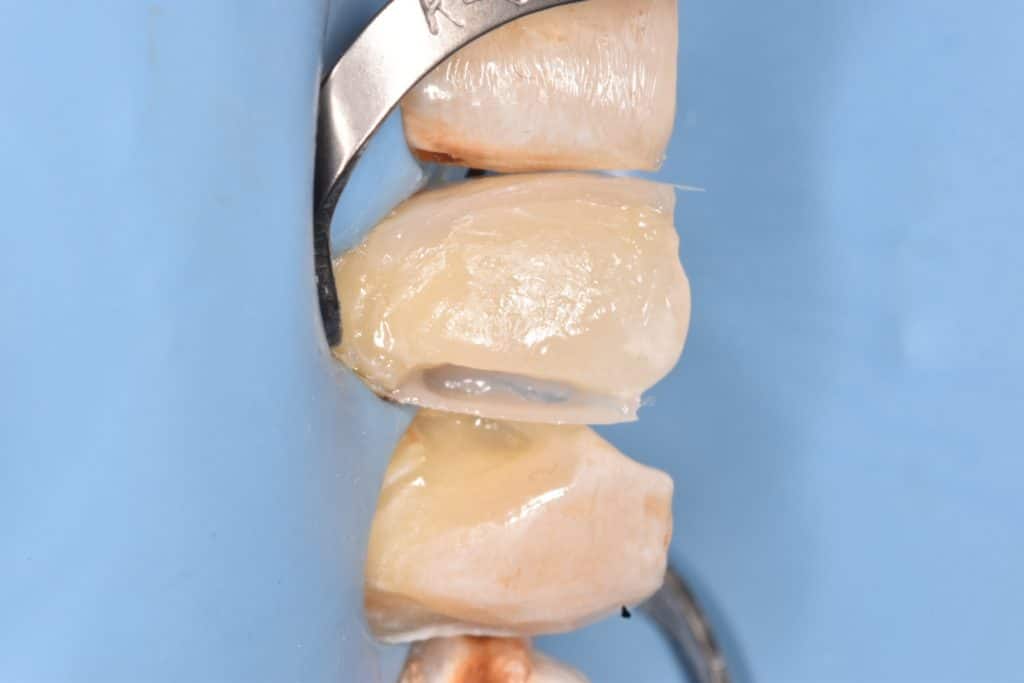

Canine isolation with b4 clamp and preparing it for restoration

Layer by layer